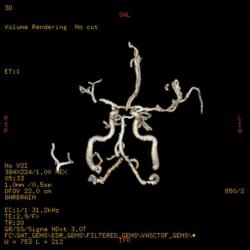

А что дают в данном случае ангиография и тем более трактография? Потеря времени ведь только, а ведь с такой патологией может быть дорога каждая минута...

Ув. Андрей! На представленных МР-томограммах при геморрагическом инсульте с большой зоной поражения, где причиной кровоизлияние иногда бывают следующие факторы: разрыв артерио-венозной мальформации, разрыв аневризмы обязательно проведение МР-ангиографии (что очень важно для хирургической тактики ведения пациента), для исключения кровоизлияния в опухоль желательно проведение не только МР-ангиографии, но и введение контрастного вещества при базовом МР-исследовании, что тоже даст дополнительную информацию. Данный случай, что предоставил нам уважаемый Евгений, МР-исследование проводилось на современном высокопольном магните, поэтому МР-ангиография и трактография не занимают много времени, а информацию для врачей лучевой диагностики и нейрохирургов предоставляют очень существенную.

Насчет контраста - безусловно, нужно вводить, никто не возражает.

А ангиография... я могу ошибаться (просто-напросто я не работаю с острой нейрохирургической патологией), но с точки зрения тактики лечения обширной внутримозговой гематомы не все ли равно, что явилось поводом для кровоизлияния? Тем более, что небольшую АВМ и тем более аневризму может быть крайне тяжело увидеть при ТАКОМ объеме гематомы.

И по-прежнему для меня остается загадкой, какую дополнительную информацию можно получить здесь при МР-трактографии.

Работая совместно с нейрохирургами, которые занимаются сосудистой патологией, перед нами постоянно ставят именно эту задачу: определить причину кровоизлияния, а отсюда и тактику доступа при нейрохирургическом вмешательстве (пункционно идти на ту или иную гематому или открытым доступом или вообще не вмешиваться и вести определенных больных консервативно). Вы правы, что при таком обширном кровоизлиянии МР-ангиография (особенно на 2-3 сутки после начала заболевания) часто оказывается бесполезной, так как из-за зоны кровоизлияния определенная часть сосудов основания мозга просто не визуализируется, или значительно смещена и деформирована именно зона интереса, что увеличивает риск неправильной трактовки данной патологии. Тогда нейрохирургам приходится применять классическую селективную ангиографию (если они действительно подозревают аневризму). Но в данном случае мы видим МР-томограммы и МР-ангиограммы в первые часы гемор.инсульта, поэтому сосуды хорошо получились. А МР-трактография (у нас нет такого оборудования как у Евгения, поэтому мы эту методику не применяем) может тоже помочь планировать операционный доступ и объем оперативного удаления гематомы с учетом видения расположения проводящих путей, их заинтересованности в патологическом процессе с целью минимальных послеоперационных осложнений и неврологического дефицита. Эта методика сейчас актуальна не только для изучения опухолей но и сосудистых заболеваний. С уважением Visus 07

В общем и целом я абсолютно согласен. Прямое показание к трактографии - это планирование операционного доступа.